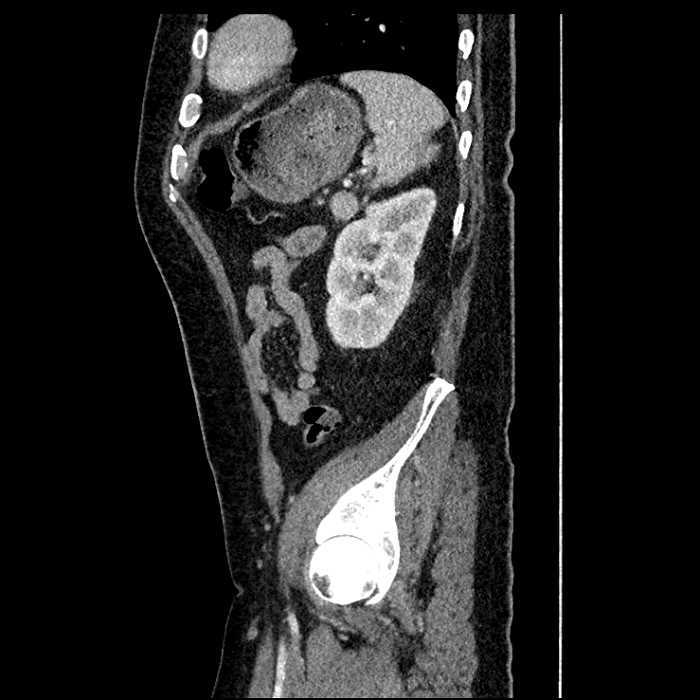

• Mild mural thickening of a segment of the sigmoid colon with adjacent fat stranding and a 1.5 cm fluid and gas collection along the tip of an inflamed diverticulum

• Loss of the normal fat plane between this collection and adjacent loops of small bowel, which demonstrate mural thickening

Acute sigmoid diverticulitis complicated by a small contained perforation and a large abscess in the right hepatic lobe. Additional small subcapsular abscesses along the anterior margin of the left hepatic lobe.

Additionally, loss of the normal fat plane between the peridiverticular collection and adjacent thickened loops of small bowel raises the potential for an enterocolonic fistula.

Hepatic abscess showing the double target sign with low density internally surrounded by a thin inner enhancing rim (red arrow) and ill-defined outer low density rim (yellow arrow). Blue arrow indicates an internal septation. Red arrows: additional smaller subcapsular abscesses. Red arrow: focal contained perforation associated with diverticulitis.